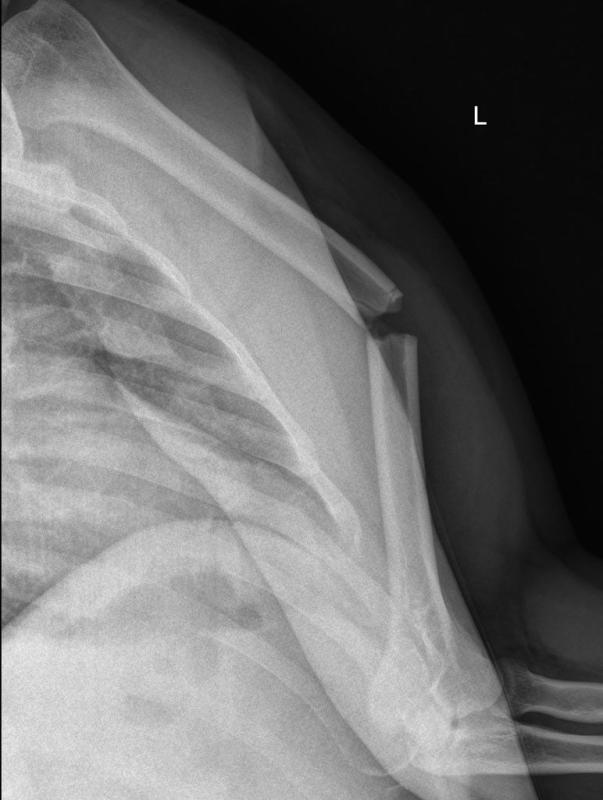

# خلع الكتف وكسر الحديبة الكبيرة: التشخيص والعلاج ## مقدمة حول إصابات الكتف إصابات الكتف شائعة، خاصة بين الرياضيين وا…